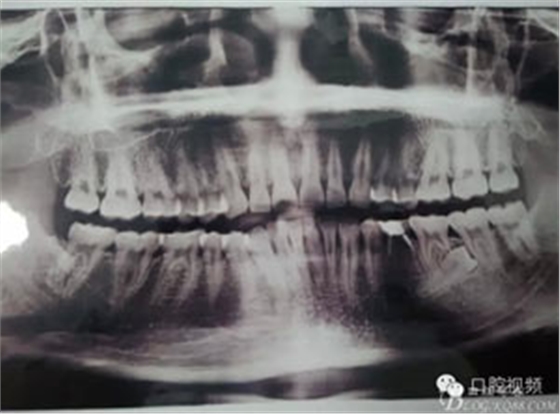

圖1.術(shù)前的全景片影像檢查,35移位至36、37之間。

患者、盧xx、男、19歲。主訴:左側(cè)下頜乳磨牙未脫落,要求檢查。??茩z查:左側(cè)下頜第二乳磨牙有充填物。無松動,全景片檢查。35移位至36、37之間。頰舌側(cè)均不能觸及隆起。CBCT檢查:35位于36、37的舌側(cè)。表面骨質(zhì)約2mm左右。35完全骨埋伏,36的遠中牙根疑是吸收。建議35暫觀察。置留不取。患者要求拔除擔(dān)心壓迫36牙根或者發(fā)生囊性變。術(shù)前簽手術(shù)同意書。